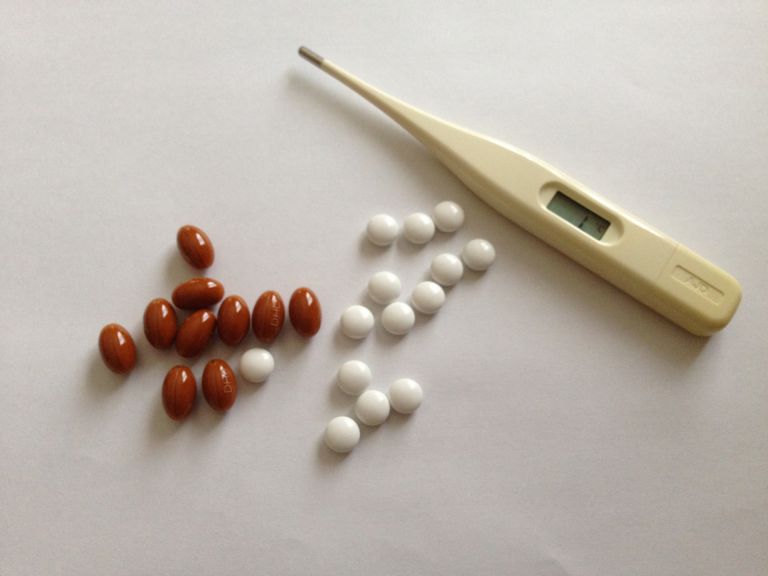

カテゴリー: 医療

新宿の多様な都市生活を支える最先端内科医療サービスの現在と未来

新宿駅周辺で支える快適都市生活と多彩な医療ネットワークの魅力

新宿で支える都市の健康多様化する都市内科医療の現在と未来

新宿の都市機能とともに進化する多様性と利便性が際立つ内科医療の今

新宿の多様化する都市生活を支える内科医療機関の進化と選択肢の広がり

新宿で暮らす人と働く人を守る多様な都市型医療と進化する内科の今

新宿の多様な人々を支える地域密着型内科医療の今と安心の仕組み

新宿の多様な都市ニーズに応える進化する内科医療と地域医療の最前線

新宿で進化し続ける内科医療ネットワークと都市生活者の健康サポート最前線